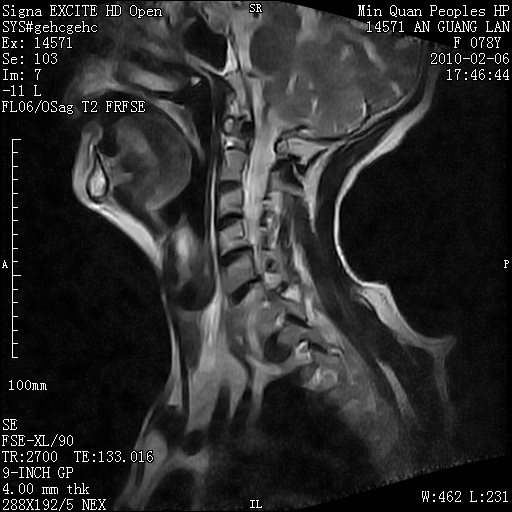

标题: MRI2763:C6、C7椎体病变性质?

f,78y,颈部与双上肢阵发性剧痛40余天。ct可见c6、c7椎体虫蚀样破坏,其间椎间隙变窄(没有图片资料可供上传)。

考虑椎体结核并椎旁脓肿。

支持 c6、7椎体结核并椎旁冷脓肿形成。

考虑:c6/7椎体结核并椎旁脓肿形成,建议增强扫描。